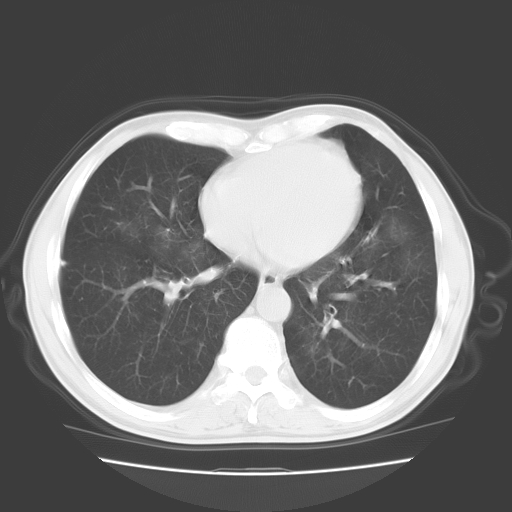

以下是引用随光逐影在2008-11-20 23:02:00的发言:[br]1)考虑左肺上叶周围型肺癌可能性大。2)两肺散在性肺泡积血。[br][br][本贴已被 随光逐影 于 2008-11-20 23:09:31 修改过]

以下是引用drzhang8888在2008-11-20 22:20:00的发言:[br]密集的短毛刺,血管集束,胸膜凹陷,周边型肺癌可能性大,另双肺多发磨玻璃影,考虑感染

以下是引用流浪星在2008-11-20 22:28:00的发言:[br]左肺上叶近外围区见一类圆形结节影,毛刺征、胸膜尾征阳性,临近肺组织见多发渗出灶。考虑1,炎症性病变。 2.周围性肺癌。建议抗炎治疗后复查。